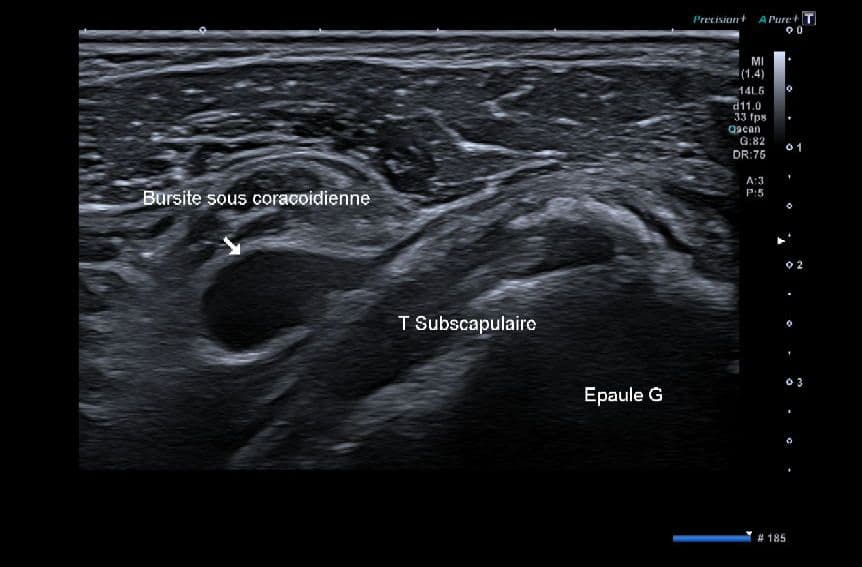

Résorption calcique aigue du tendon sous-scapulaire

Échographie

Epanchement réactionnel dans la bourse sous coracoïdienne adjacente.